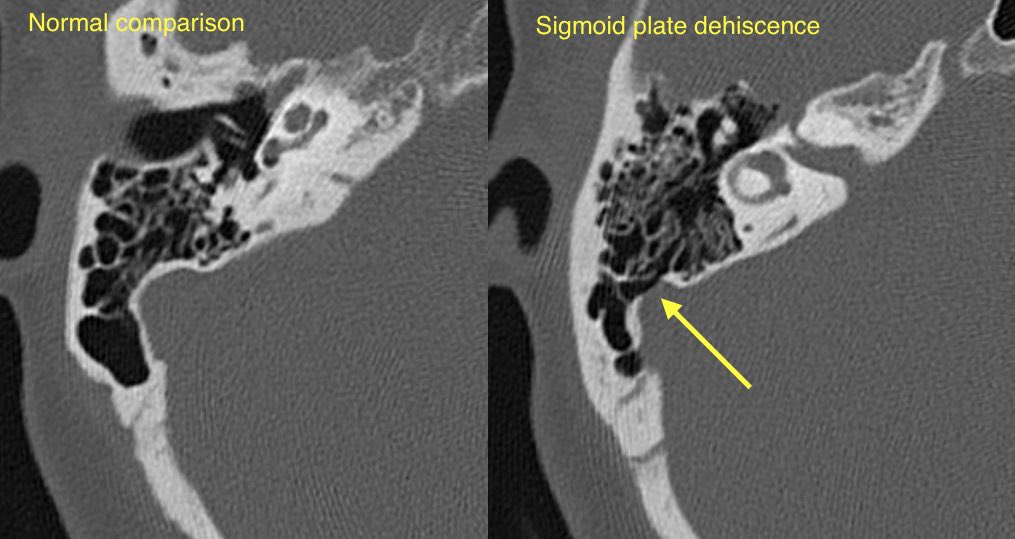

🔷SIGMOID SINUS WALL ANOMALIES

1️⃣Sigmoid plate dehiscence

2️⃣Sigmoid sinus diverticulum

🔹Sigmoid plate dehiscence: Thinning or absence of the normal cortical bone covering the sigmoid sinus resulting in direct contact of the venous sinus wall with mastoid air cells

🔹Sigmoid sinus diverticulum: Lateral outpouching of the transverse sigmoid sinus junction with intrusion into the adjacent bone

💡 Sigmoid plate dehiscence w/ or w/o diverticulum is one of the most common imaging abnormalities at CT for pulsatile tinnitus (up to 40%). These findings are more prevalent in patients with TSS and IIH